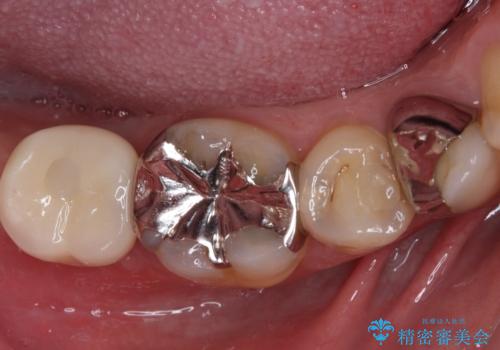

骨格的に下顎骨が前方にあり、歯列の幅も下顎の方が大きいため、奥歯に負担のかかりやすい咬合でした。

大臼歯部は、上下左右ともに咬合により問題が生じており、骨格的な問題から積極的な治療をするべきか判断の難しい状況でした。

臼歯部は痛みが生じている歯に絞って処置を行い、それ以外については手を加えず、現状維持を心がけることとしました。